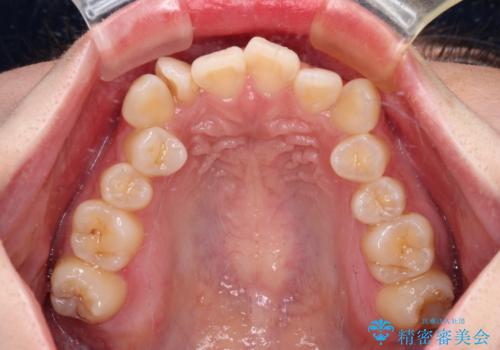

- 上下前歯のデコボコを気にして来院された患者様です。

口元の突出感はあまりなかったものの、デコボコを非抜歯で改善すると出っ歯になる可能性があるため、上下左右の第一小臼歯4本を抜歯し、ワイヤー装置にて矯正治療を行うこととしました。

口元の突出感はなかったものの、捻転や八重歯を改善するために補助装置を併用する必要がありました。

予定の2年半を越えてしまいましたが、無事にきれいな口元に仕上げることができました。